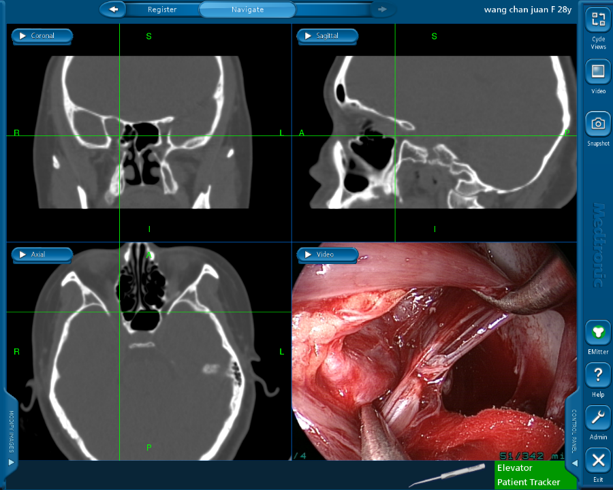

? ? ? 手術(shù)中,吳文燦首先采用新型磁導(dǎo)航技術(shù)對腫瘤精準(zhǔn)定位與實時追蹤,然后借助內(nèi)窺鏡很好的照明與放大倍率,采取內(nèi)窺鏡微創(chuàng)技術(shù)將腫瘤與周圍組織之間的粘連帶極其小心地分離。

? ? ? 在剝離過程中,當(dāng)處理海綿竇深部那一部分腫瘤時,只見腫瘤組織不停地搏動,突突地往外“冒”血。但吳文燦沒有絲毫驚慌,表現(xiàn)得異常冷靜,一手既持鏡又持吸引器等2把器械,另一手持剝離子與一把抓鉗,雙手持4把器械,硬是把腫瘤一點點從海綿竇深處“逼”出來,成功“拆彈”。